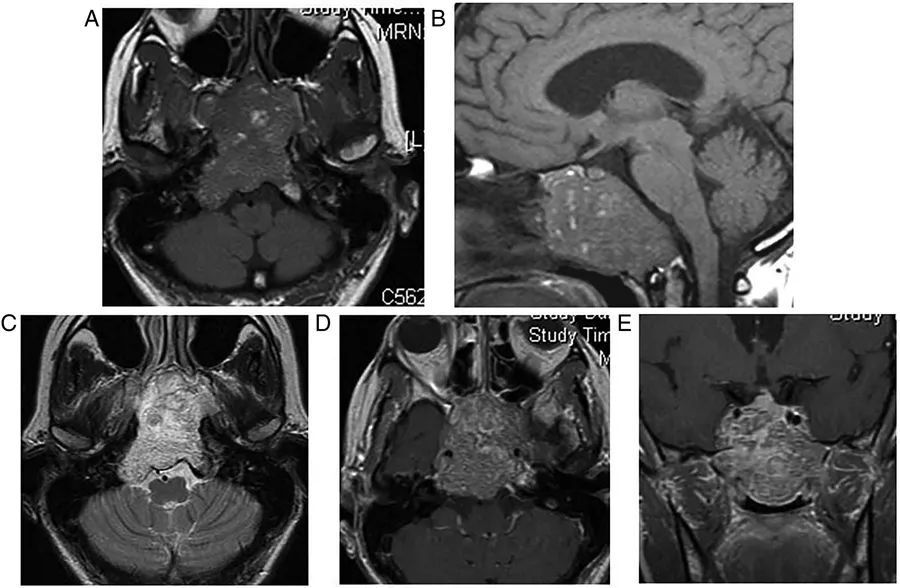

图2  肺部原发肿瘤转移。左侧桥小脑区可见转移灶,当桥小脑区结构不清时,有时很难区别是轴内病变还是轴外病变。这种不均匀的强化提示转移瘤,小脑无水肿则提示轴外病变

图3  结核瘤。左侧小脑表面可见一环形强化的结核瘤,膨胀进入桥小脑角区,并呈现出类似于轴外病变的外观,不过由于存在小脑水肿,该病灶更可能源于轴内。此外,右侧外侧裂可见脑膜强化,即脑膜炎的证据

图4  巨大椎基底动脉连接处动脉瘤。患者表现为延髓症状,影像学显示左侧桥小脑角区不规则占位性病变,并呈流空信号,第四脑室受压变形,通过血管造影最终证实了巨大动脉瘤的诊断

图5  右侧桥小脑角区脑膜瘤。可见类圆形病灶压迫右三叉神经和脑桥,增强扫描可见显著均匀强化,强化的硬脑膜尾沿着颞骨岩部向下延伸